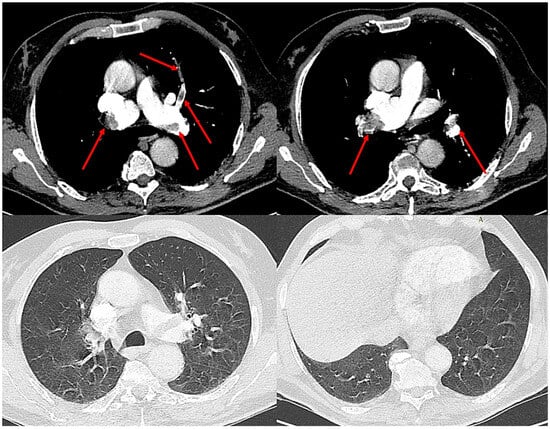

2. Case Presentation